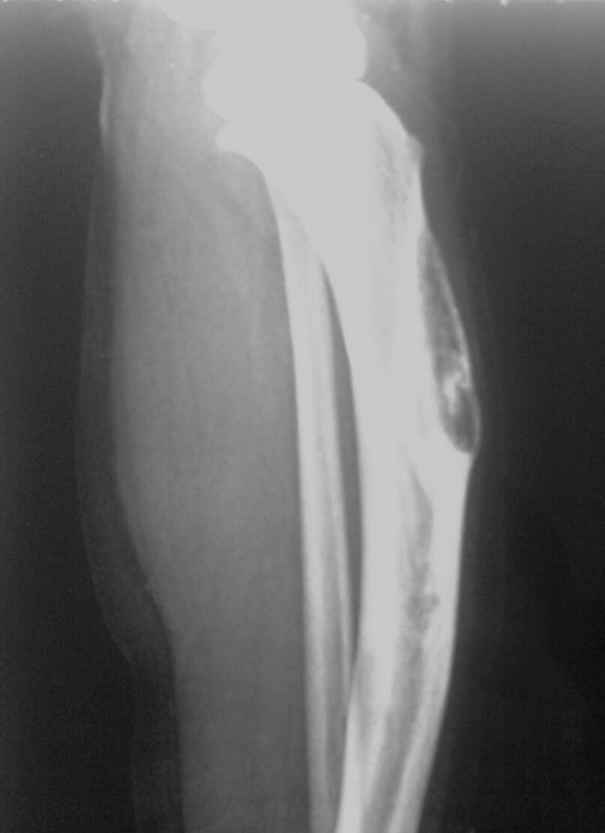

女孩4岁,左小腿肿物1年余,无痛,有跛行。胫前有肿物,质硬,无压痛。

胫骨增粗膨大,弯曲变形,多处骨皮质见囊性破坏,且呈纵轴发展,与正常骨分界欠清,破坏区内见高密度影。腓骨也累及。考虑骨纤,其他骨病变不排外。

胫骨增粗膨大,弯曲变形,多处骨皮质见囊性破坏,且呈纵轴发展,与正常骨分界欠清,破坏区内见高密度影。腓骨也累及。考虑骨纤,